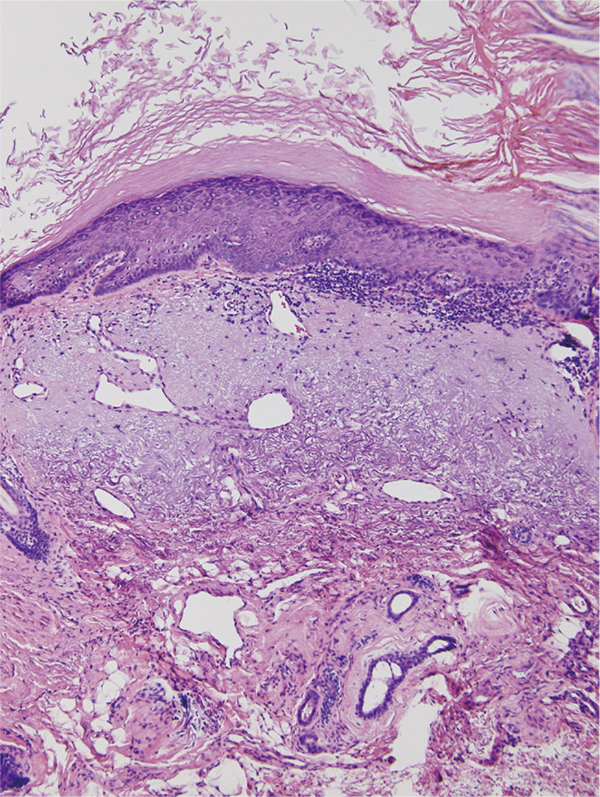

スキン-テアが好発する高齢者の皮膚では、表皮の菲薄化と表皮突起の平坦化、真皮乳頭層の毛細血管係蹄の消失が観察される。この変化は高齢者においては軽微な外力により、容易に表皮剥離が起こる機序を示唆するものである。また、高齢者の表皮では、皮脂分泌の減少、セラミドや天然保湿因子の減少が起こり、バリア機能が低下する。一方、真皮の老化には、生理的老化(chronological ageing)と光老化(photo ageing)の2つのメカニズムが存在する。スキン-テアの発症にはこの光老化を理解する必要があることが示唆されている8)。

これは、紫外線障害に対する代償的産生と考えられており、結果として不規則な塊状沈着としてエラスチカ・ファンギーソン染色で観察できる。ここには、エラスチン以外にもフィブリリン、バーシカンや接着分子であるフィブロネクチンが含まれる。この現象は高齢者の露光部から採取した病理標本で、真皮乳頭層から網状層にかけて淡く好塩基性に染まる線維塊として容易に観察できる(図3)。紫外線が惹起する変化であり、日光角化症などの病理標本で高率にみられる。

高エネルギー紫外線は線維芽細胞に対し細胞傷害性を有する。細胞傷害を来さない量の紫外線はコラーゲンの産生を低下させ、matrix metalloproteinase(MMP)の産生を亢進させる10)。これらは細胞膜表面に存在するインターロイキン(IL)-1、表皮細胞増殖因子や腫瘍壊死因子-αのレセプターを通して、遺伝子レベルで制御される。その結果、プロコラーゲン遺伝子の発現は阻害され、MMPの転写は亢進する。UVAを用いた検討では、MMP-1、3、9は産生が亢進するが、MMPに抑制的に働くtissue inhibitor of MMP(TIMP)には影響を与えないとされ、これらのアンバランスにより光老化が進むと考えられている11)。ムコ多糖は生理的老化でもその量は減少し、60歳で乳児の約25%となる。しかし、光老化ではグリコサミノグリカン量は増加することが知られている12)。図3. 日光弾性線維症の病理組織学的所見 記事/インライン画像